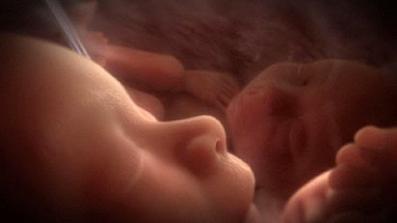

Jak asi víte, těhotenství je členěné na tři časové úseky, kterým říkáme trimestry – každý z nich trvá tři měsíce. Každý z trimestrů je zcela specifický, probíhají v něm určité charakteristické změny, podstupuje se vyšetření a nesou s sebou jiné pocity a obavy nastávající maminky.

Druhé tři měsíce těhotenství jsou pro spoustu žen nejkrásnějším a nejpříjemnějším obdobím za celou dobu těhotenství.

zázrak lidské života na videu